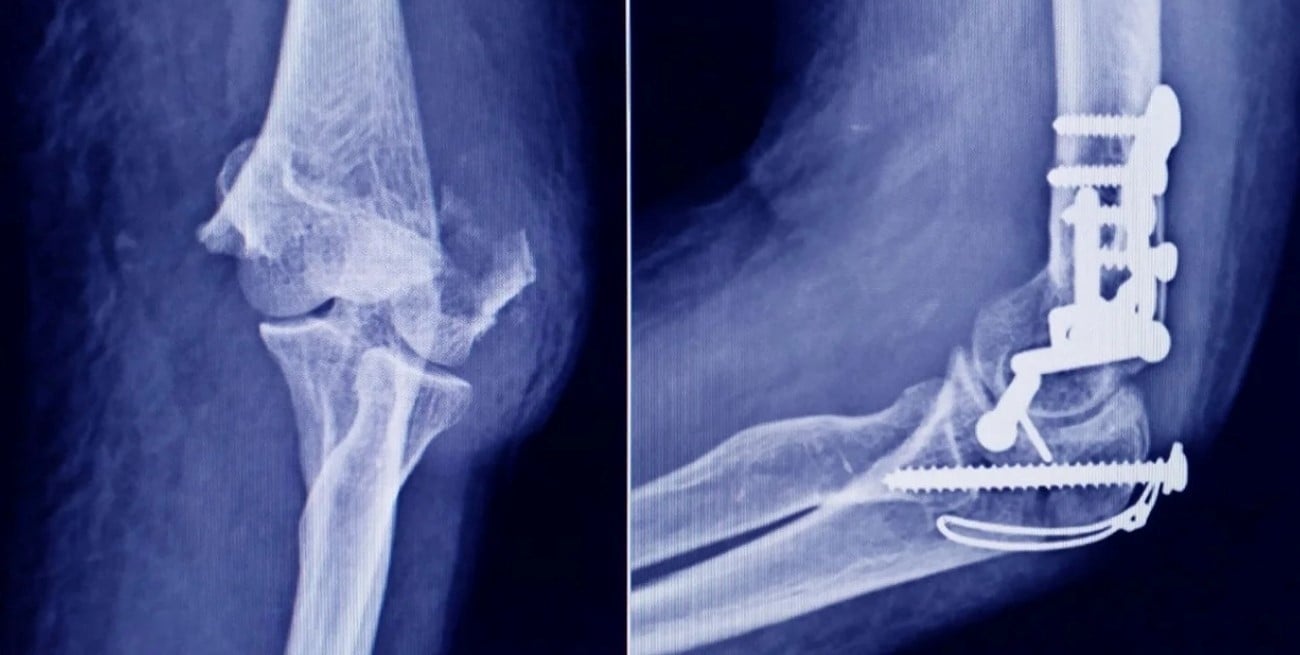

Además del tornillo falsificado, se encontraron otros 19 implantes —tornillos óseos de titanio— rotulados como pertenecientes a fabricantes internacionales. Sin embargo, estos productos no pudieron ser validados por los importadores oficiales en Argentina.

La empresa titular del registro sanitario informó que no había ingresado esos lotes al país ni reconocía las unidades como propias. Incluso, se detectaron inconsistencias en el rotulado, que mencionaba vínculos comerciales inexistentes entre firmas internacionales.

La situación se agravó por la falta total de documentación que acreditara la procedencia de los productos. El responsable del establecimiento no pudo presentar facturas, registros de importación ni certificados sanitarios.

En términos técnicos, esto implica una ruptura completa de la trazabilidad, un elemento central en el control de dispositivos médicos. Sin esa información, resulta imposible garantizar cómo fueron fabricados, transportados o almacenados los insumos.

Para los tornillos de titanio de origen desconocido, el riesgo radica en la falta de garantías sobre su calidad. No se puede asegurar que los materiales sean aptos para uso médico ni que cumplan con los estándares de biocompatibilidad.

También se desconoce si los productos fueron almacenados en condiciones adecuadas o si han sido retirados del mercado en otros países por fallas de funcionamiento.